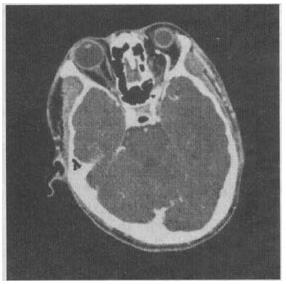

男性,28岁。外伤后出现眼球外突,扪之有搏动感,增强CT扫描见图示,应诊断为()。

A、颈内动脉海绵窦瘘

B、眼眶内AVM

C、眼眶内AVF

D、眼眶内AVM并AVF

E、眶内异物

A